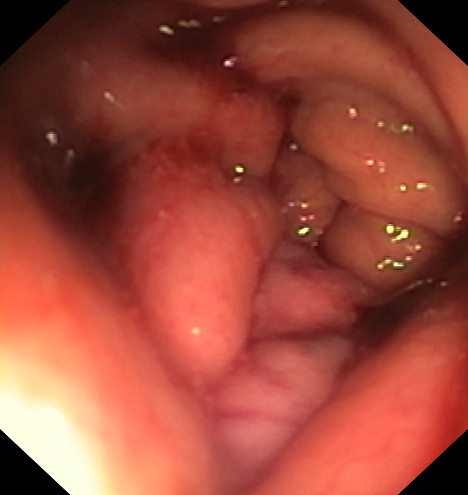

La gastroplastia endoscópica mediante la técnica endomanga se realiza por el gastroscopia, bajo anestesia general y dura aproximadamente entre 25 y 35 minutos. Mediante la endoscopia se realizan unos 18 pliegues definitivos a lo largo de todo el cuerpo gástrico, reduciendo de manera importante su capacidad de apertura, acortándolo y estrechándolo. Gracias a esta reducción los pacientes disminuyen la sensación de hambre.

Mediante un sistema de sutura acoplado a un endoscopio, se sutura el estómago “desde dentro” dándole un aspecto similar al conseguido por la cirugía de gastrectomía vertical laparoscópica (manga gástrica quirúrgica), pero con menor riesgo quirúrgico y muy buenos resultados a medio y largo plazo. De esta manera se limita la cantidad de comida que puede entrar en el estómago e igualmente hace que la digestión sea más lenta, favoreciendo enormemente la saciedad y la pérdida de peso. Es una técnica definitiva, pero por vía oral, ni realizar heridas abdominales ni cicatrices.